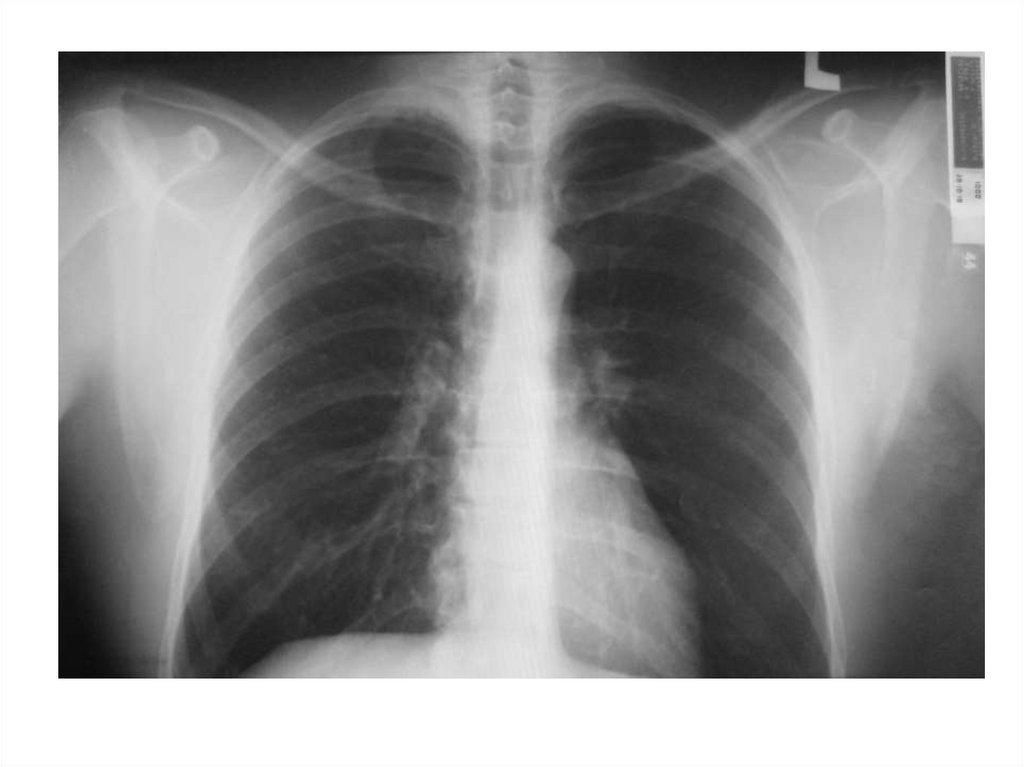

4. Повышенная воздушность

Эмфизема легких – признаки:

• увеличенные легочные поля

• низкое стояние диафрагмы

• грудина смещена кпереди, большое

ретростернальное пространство (на боковом

снимке)

5.

6.

7.